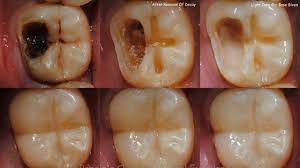

3. A deep blind pocket will be formed between the impacted wisdom teeth and the surrounding gums, which can easily cause food residues to stick to the tooth surface, thereby accumulating for a long time, gradually forming bacterial infection, and deep caries can reach Deep in the dentin, close to the pulp, or may have affected the pulp, causing severe pain.

In another situation, when you have a toothache, you go to the hospital for a check-up and find out that it may be due to deep tooth decay, causing the root of the tooth to become infected, inflamed and painful.

After examination, the doctor determined that the tooth nerve was infected and required root treatment. There were many cavities in the mouth and multiple fillings were needed.

This type of tooth decay can be caused by not paying attention to oral hygiene, not cleaning and cleaning your teeth regularly, and having regular check-ups.